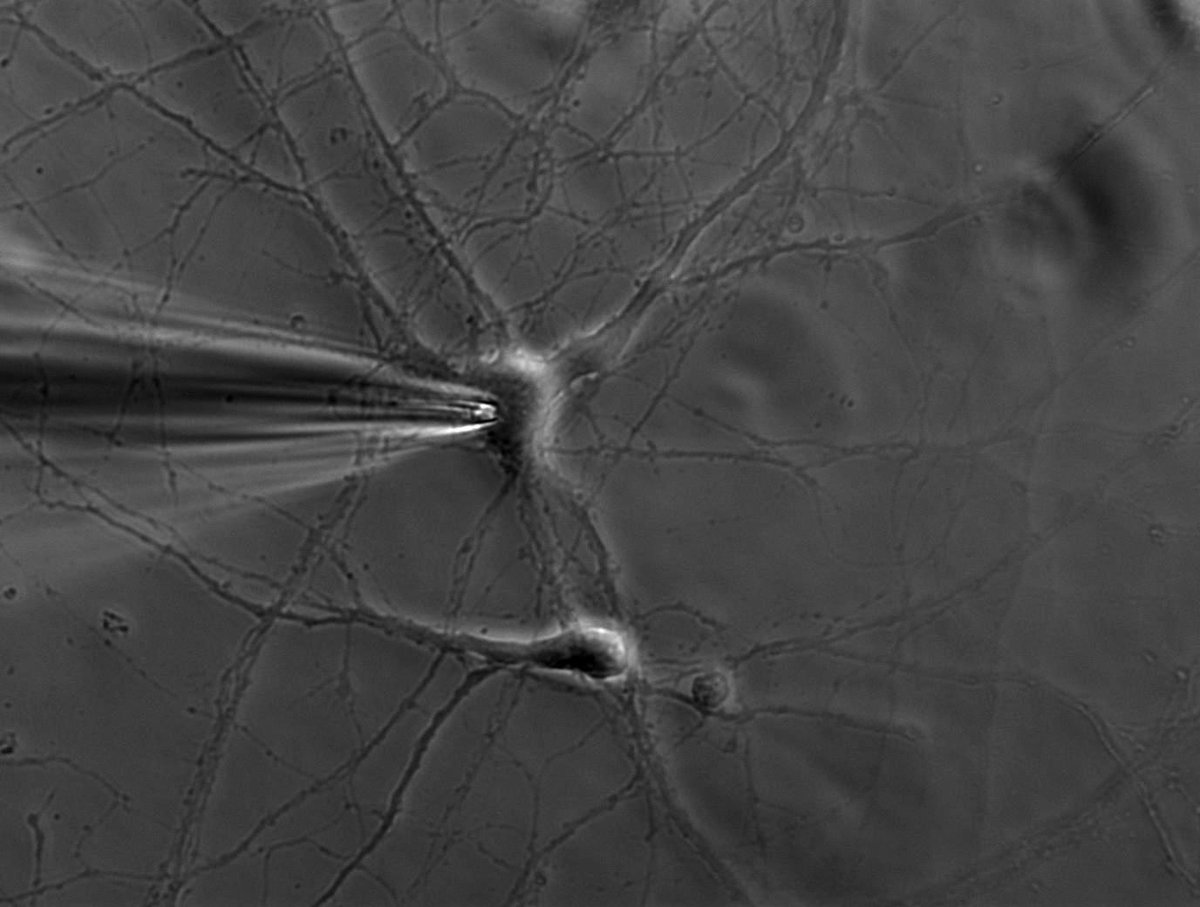

Twitter thesis day 3: Recording of human brain activity

This thread's a little longer and it's still impossible to cover this topic in anything close to a comprehensive fashion. But here are some highlights: Historically, neuroscience has been limited mostly to animal experimentation. The electrophysiological, histological and biochemical methods classically used to study the brain are far too invasive to use in humans